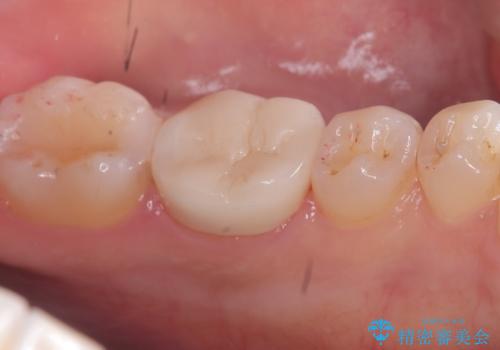

- 主訴:強く噛んだら歯がポロポロ欠けてきた。

左下6番目の歯の咬合面にプラスチックの材料が詰まっており、歯質がドーナツ状にしか残っていなかったため、歯質幅が比較的薄かった場所が欠けてしまったようでした。

今後の破折リスクを説明し、セラミッククラウンでのやり替えとなりました。

頬舌的レジンインレーが入っており、歯質幅の薄かった且つ強く咬合していた遠心側歯質が欠けてしまっていました。また新しい窩洞のインレーを入れても、近心側歯質の破折のリスクは抱えたままになることから、クラウンでの修復をおすすめし審美性・適合性のよいセラミッククラウンでのやり替えとなりました。